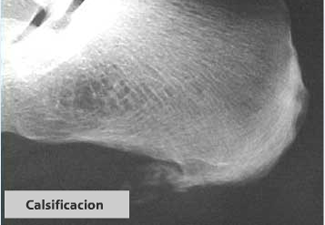

Espolón calcaneo.

Imagen radiográfica de calcificaciones de la fascia plantar.